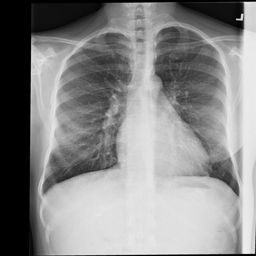

Deployments of artificial intelligence in medical diagnostics mandate not just accuracy and efficacy but also trust, emphasizing the need for explainability in machine decisions. The recent trend in automated medical image diagnostics leans towards the deployment of Transformer-based architectures, credited to their impressive capabilities. Since the self-attention feature of transformers contributes towards identifying crucial regions during the classification process, they enhance the trustability of the methods. However, the complex intricacies of these attention mechanisms may fall short of effectively pinpointing the regions of interest directly influencing AI decisions. Our research endeavors to innovate a unique attention block that underscores the correlation between 'regions' rather than 'pixels'. To address this challenge, we introduce an innovative system grounded in prototype learning, featuring an advanced self-attention mechanism that goes beyond conventional ad-hoc visual explanation techniques by offering comprehensible visual insights. A combined quantitative and qualitative methodological approach was used to demonstrate the effectiveness of the proposed method on the large-scale NIH chest X-ray dataset. Experimental results showed that our proposed method offers a promising direction for explainability, which can lead to the development of more trustable systems, which can facilitate easier and rapid adoption of such technology into routine clinics. The code is available at www.github.com/NUBagcilab/r2r_proto.